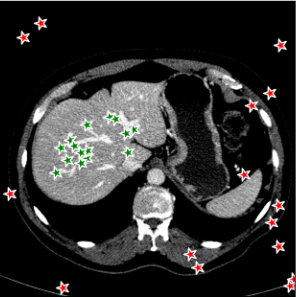

Points are the most fundamental interactions in semi-automatic annotation tools, but also most unpredictable. To train a new point-based prompt tailored to a specific annotation task, a stochastic process is employed wherein points are randomly sampled from the interval of within both the background and foreground regions of each annotated slice during every iteration of the training process. In this work, three distinct point selection schemes has also been investigated, namely ‘uniform’, ‘center’ and ‘boundary’. An example is illustrated in Fig. 5. In the case of uniform sampling, points are random selected with uniform distribution within the mask region. For center sampling, we primarily selected the points at the central location within the target region, by applying a distance transform. Conversely, the boundary sampling mainly selects the point near the boundary.

For 3D dataset, the SAM model will be initially trained on several randomly selected annotated slices, and then tested on the remaining slices. For 2D dataset, such as Kidney-US and Nuclear-Hist, the SAM model will be initially trained on several randomly selected cases, and test on other cases. We randomly sampled points from both foreground and background regions to train the new prompt. Each case will be trained and tested, individually. Figure 7 demonstrated the performance of the point-based SAM model. As the figure shows, single point on the target has shown remarkable segmentation performances using SAM even with only 2 annotated slices for the prompt training, compared to the original SAM model. Segmentation results of Kidney-CT are visualized in Figure 8. Segmentation results of one test slice is shown to demonstrate the significant improvement of SAM . Comparison results with other state-of-the-art segmentation results are shown in Table 2 including both fully-supervised (such as nnUNet, UNetr), fine-tune based SAM segmentation method (such as MedSAM, MSA).

The segmentation results of different point selection schemes for the Kidney-CT dataset is demonstrated in Figure 9. Uniform random selection scheme shows slightly better variation compared to other scheme but there is no significant differences between each scheme entirely.